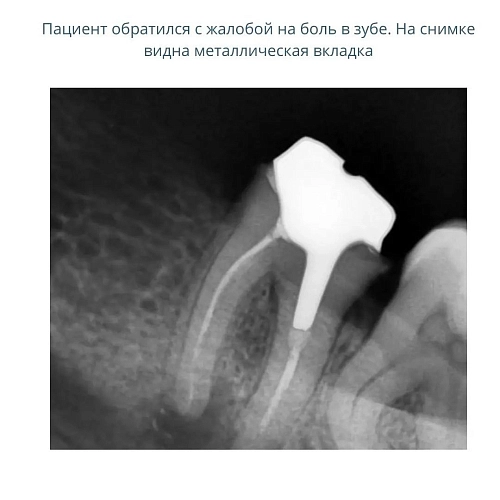

Пациентка обратилась в клинику с жалобой на боль в зубе.

На зубе была ранее установлена коронка.

При снятии коронки была обнаружена металлическая вкладка,которую необходимо было извлечь для перелечивания корневых каналов.